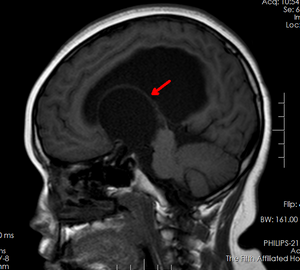

芳芳(化名)今年14岁,正值花季年龄的她却有着自己的烦恼。原来芳芳的生长发育跟同龄人相比明显迟缓,不但个头低于同龄人,并且有喝水多、上厕所频繁的现象,因此也变得不愿与人交流。家人不敢掉以轻心给女儿查了个头部的磁共振。不查不知道,这一查居然发现芳芳脑子正中间的位置有一个巨大“水球”,医学上叫做“鞍上池蛛网膜囊肿”,正是这个大水球压迫丘脑等重要结构引起了芳芳发育慢、尿崩等症状。当地医院条件有限,于是转入郑州大学五附院神经外科三病区就诊。付旭东主任带领其团队认真研究了患者的影像学资料,制定了神经内镜造瘘打开蛛网膜囊肿侧壁,把“死水”变成“活水”的手术方案。手术过程很顺利,术后喝水多、小便频繁的症状明显改善。由于神经内镜创伤很小,芳芳术后很快康复出院。

术后7天复查囊肿明显缩小